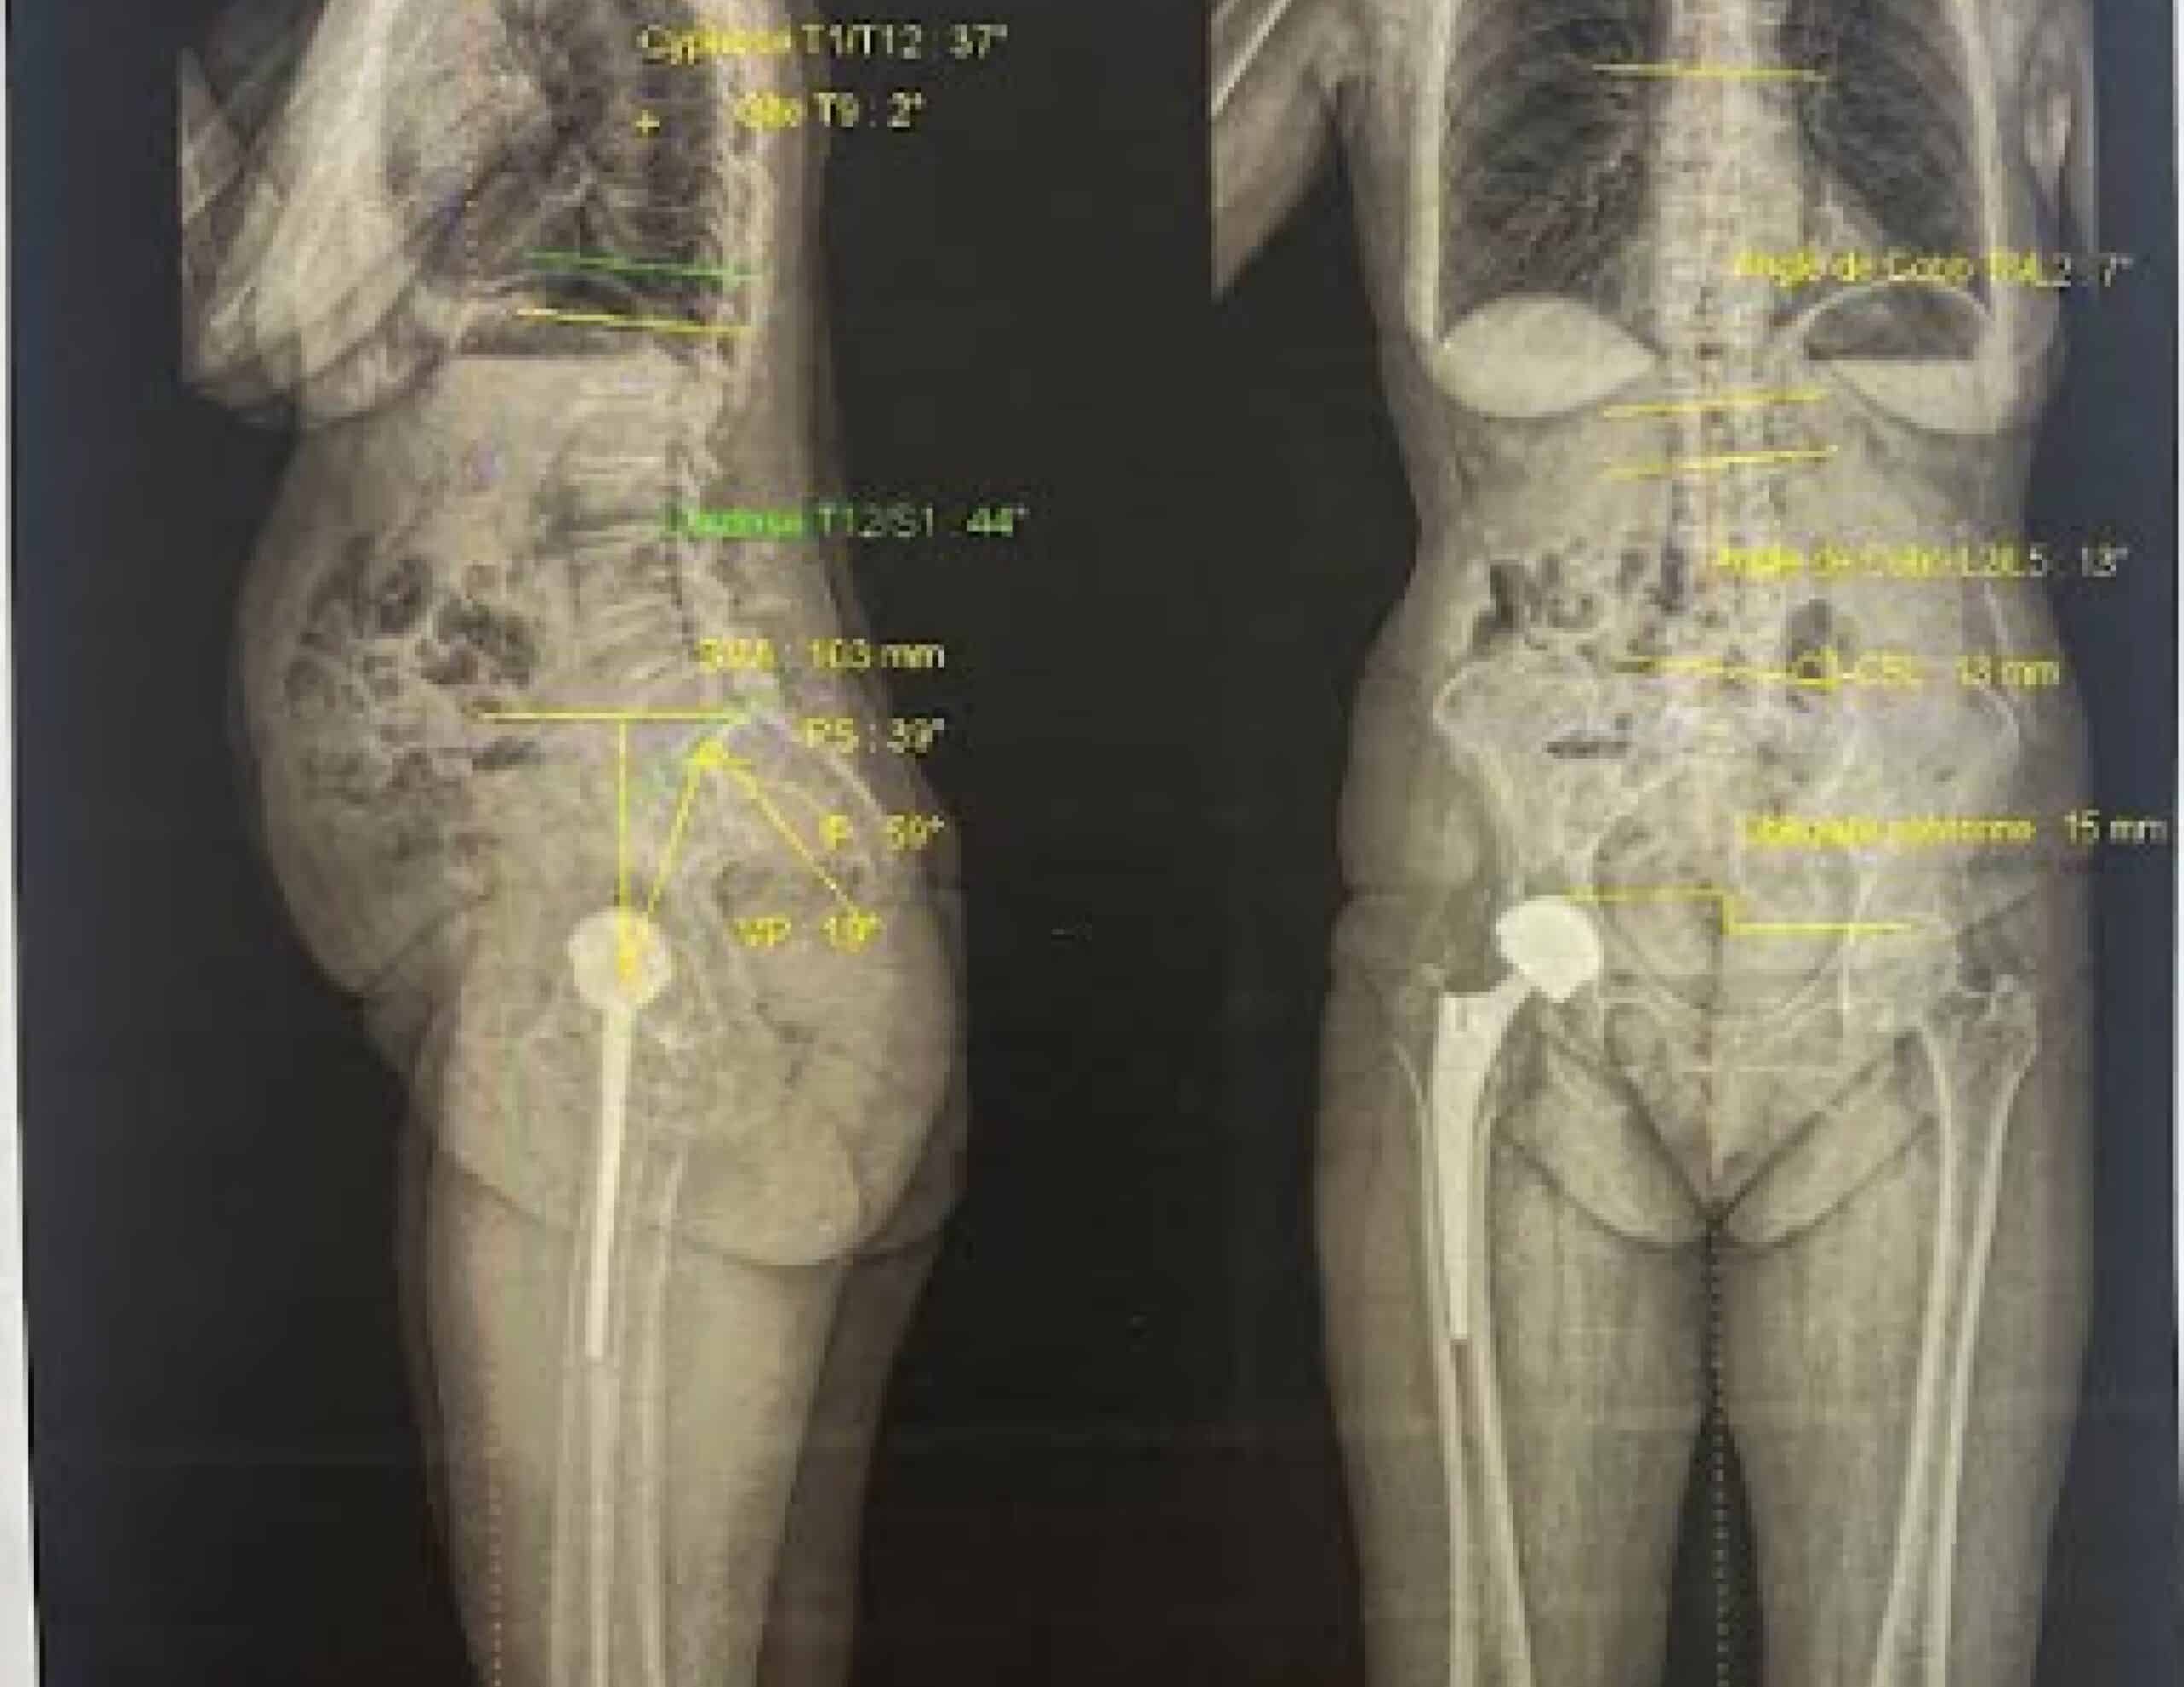

L’imagerie EOS : une vision globale du squelette

L’imagerie EOS est une technique radiologique à faible irradiation qui permet de réaliser une exploration du corps entier en position debout. Elle offre une vue d’ensemble du rachis et des membres inférieurs, et permet de visualiser et quantifier les déviations dans les plans frontal, sagittal et axial.

- Utile dans les cas de scoliose ou de bassin oblique

- Permet la quantification des paramètres lombo-pelvi-fémoraux (relations entre le rachis lombaire, le sacrum , le pelvis et le fémur )

- Met en évidence les déformations des membres inférieurs : genu valgum, genu varum, flessum du genou ou de la hanche

- Mesure la longueur des segments osseux et détecte une inégalité de longueur des membres inférieurs